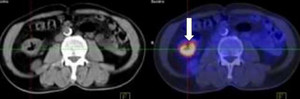

Các nhà nghiên cứu tách tế bào T (một loại bạch cầu có chứa các thụ thể nhận diện tế bào ưng thư) từ máu của 16 bệnh nhân có khối u rắn, bao gồm ung thư ruột kết, vú hoặc phổi. Họ xác định hàng chục thụ thể có khả năng nhận diện các tế bào ung thư tương ứng với từng bệnh nhân. Sau đó, nhóm nghiên cứu chọn tối đa ba thụ thể đối với mỗi bệnh nhân và sử dụng CRISPR để thêm gen của những thụ thể này vào tế bào T của người đó trong phòng thí nghiệm.

Các nhà khoa học đã nuôi cấy thêm nhiều tế bào đã qua chỉnh sửa. Sau đó, họ truyền vào người từng bệnh nhân những tế bào miễn dịch mới này. Các tế bào di chuyển đến các khối u và xâm nhập chúng.

Trong trường hợp của 6 bệnh nhân, liệu pháp thử nghiệm đã thành công ngăn chặn sự phát triển của các khối u. Trong 11 người còn lại, bệnh ung thư của họ tiếp tục tiến triển xấu. 2 người phát sinh tác dụng phụ liên quan đến liệu pháp - một người bị sốt và cảm lạnh, người còn lại bị choáng. Tất cả các tình nguyện viên đều trải qua tác dụng phụ từ các đợt hoá trị trước đó.